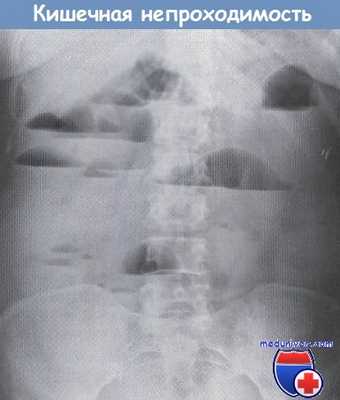

• Уровни жидкости и растяжение толстой кишки: соответствуют уровню обструкции; «переходная точка» соответствует уровню механической обструкции: наличие воздуха, определяемого в прямой кишке, подозрительно в отношении псевдообструкции или энтерита.

• Дилатация толстой кишки с симптомом «кофейного зерна»: заворот сигмовидной кишки (ось направлена к ЛВК) или слепой кишки (ось направлена к ПНК).

Уровни газа и жидкости при кишечной непроходимости.